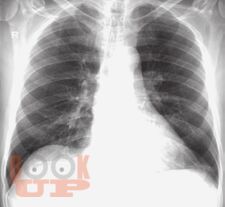

В настоящей монографии подробно описаны и проиллюстрированы изменения легких, сердца и костной системы при различных патологических состояниях в пульмонологии, кардиологии и ревматологии. Сопоставлены клиническая и рентгенологическая картины при различный нозологических формах проявления многих заболеваний. Все представленные результаты рентгенологических исследований верифицированы и подтверждены клинически. Монография предназначена для врачей-рентгенологов, пульмонологов, кардиологов и ревматологов, а так же врачей других специальностей, занимающихся диагностикой и лечением органов грудной клетки.